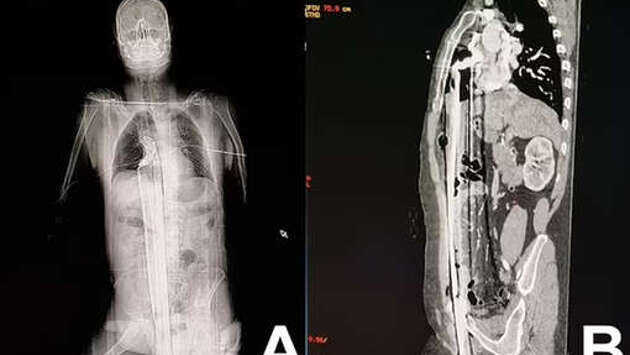

В Бразилии мужчина выжил после страшного инцидента на стройке: он упал с высоты пяти метров на железный прут. Об этом сообщает Daily Mail. Инцидент произошел на стройплощадке в городе Куритиба: 57-летний рабочий находился на строительных лесах, когда поскользнулся и полетел вниз. Падение пришлось на торчавший металлический штырь, который пронзил мужчину вдоль: штырь вошел через пах, поразил печень и достиг верхней части диафрагмы, едва не задев сердце. Мужчину на скорой доставили в больницу, где врачи по частям достали из него штырь, зашили раны и сделали переливание крови. Через два дня пациента перевели из реанимации в общую палату: к этому моменту он самостоятельно передвигался и принимал пищу. Пациента выписали на 12-й день, позже ему провели операцию, чтобы восстановить поврежденную часть уретры, на которой образовался рубец.